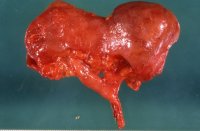

Makroskopisch findet sich infolge der eingezogenen Narben eine höckrige Oberfläche der Nieren, deren Gewicht deutlich verringert ist. Es kann sich um total geschrumpfte Organe mit bindegewebiger Umwandlung von Rinde und Mark bzw. großbuckeligen Formen mit einzelnen groben Einziehungen und Verschmälerung des Parenchyms handeln (s. Abbildung 2, 3b). Auf der Schnittfläche ist die Mark-Rinden-Zone oft nicht abgrenzbar. Die Narben verlaufen keilförmig, teilweise bis ins Nierenbecken (s. Abbildung 4b). Das Hilusfettgewebe ist vermehrt ("Vakatwucherung") (s. Abbildung 18)

Die Abbildungen zeigen pyelonephritische Schrumpfnieren, die im jüngeren Erwachsenenalter wegen Hypertonus bzw. rezidivierenden Harnwegsinfekten auffielen, aber mit Wahrscheinlichkeit im Kindesalter entstanden sind (Abbildung 2,3,4,18).